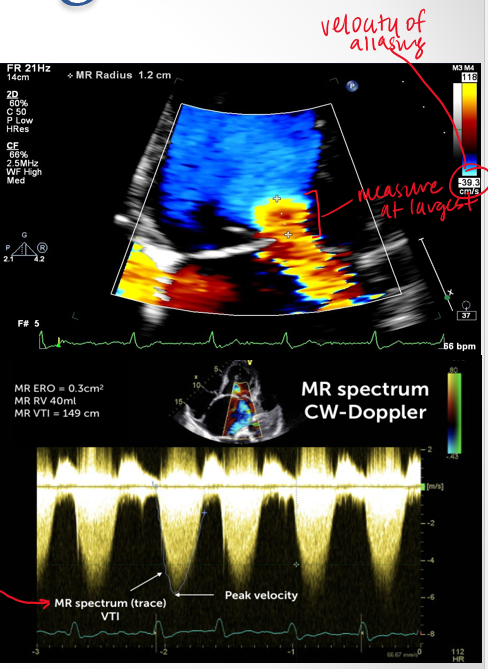

how do you obtain PISA measurement

4ch view

zoom in on MV

color doppler

lower color scale below 40

measure PISA radius

measure max velocity of regurg jet using CW doppler

what numbers does the PISA measurement give us?

velocity of aliasing

pisa radius

VTI trace

lesion severity (EROA—> size of defect) and volume overload (Rvol → how much blood is regurgitant)

what is mild moderate and severe EROA (Cm²)

mild <.2

moderate .2-.39

severe : >/= .4

what is mild moderate and severe Rvol?

mild <30

moderae 30-59

severe >/= 60